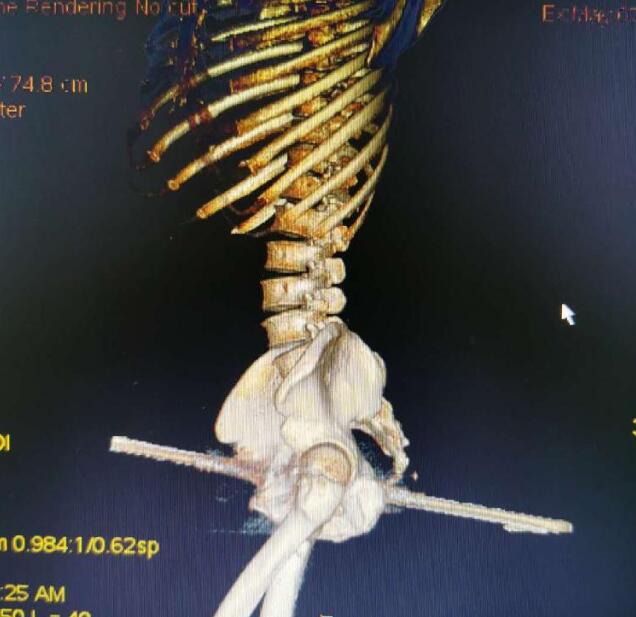

到達醫(yī)院后,消防員們被醫(yī)院工作人員帶到手術(shù)室外,按要求換好衣服后進入手術(shù)室,“當(dāng)時看見一名男子側(cè)躺在手術(shù)臺上,一根鋼筋從臀部穿過男子身體! 天文特勤站隊長助理耿家家說,據(jù)他目測,臀部那一側(cè)鋼筋裸露在外有20厘米長,另一側(cè)裸露在外10厘米左右,鋼筋直徑在1.5厘米左右。后經(jīng)測量,鋼筋長度在45厘米左右。

據(jù)介紹,因為鋼筋已經(jīng)穿過男子身體,取出鋼筋需要將多余的部分切斷。而切斷鋼筋有兩種方案,一是用無齒鋸鋸斷,但是會產(chǎn)生火花,也有一定的導(dǎo)熱性,可能會燒傷皮膚。第二種方案是用荷馬特剪切鉗將鋼筋剪斷。

經(jīng)過和醫(yī)生短暫商量后,消防員決定使用荷馬特剪切鉗剪斷!耙幻绬T操作剪切鉗,另外四名消防員從左右兩側(cè)扶住荷馬特,穩(wěn)住剪切鉗重心,醫(yī)生扶住鋼筋,避免晃動! 從進入手術(shù)室到結(jié)束,前后經(jīng)過5分鐘,鋼筋順利被剪斷。

據(jù)了解,被鋼筋刺穿身體的男子44歲,當(dāng)天在工地作業(yè)時,不小心從1米多高的地方摔落,被地上豎立的鋼筋從右臀部向前側(cè)貫穿。

“雖然鋼筋刺穿了身體,但幸運的是避開了血管、坐骨神經(jīng)、股動脈等重要位置!敝貞c市東南醫(yī)院骨科副主任譚云說,經(jīng)過前期治療患者的生命體征比較穩(wěn)定,院方經(jīng)過會診提出兩種方案,一是將右臀部表面組織全部切開,露出鋼筋。另一中方案就是將鋼筋從身體內(nèi)抽出。

“考慮到第一種方案對患者損傷較大,決定采取第二種方案!弊T云說,雖然鋼筋在工地已經(jīng)被截斷,但還是留下不少,并且鋼筋為螺紋鋼,如果按正常的方式抽出,會帶出部分體內(nèi)組織,對患者造成更大的傷害,為了最大限度減少患者損傷,也方便操作,決定求助消防用專業(yè)工具剪切。